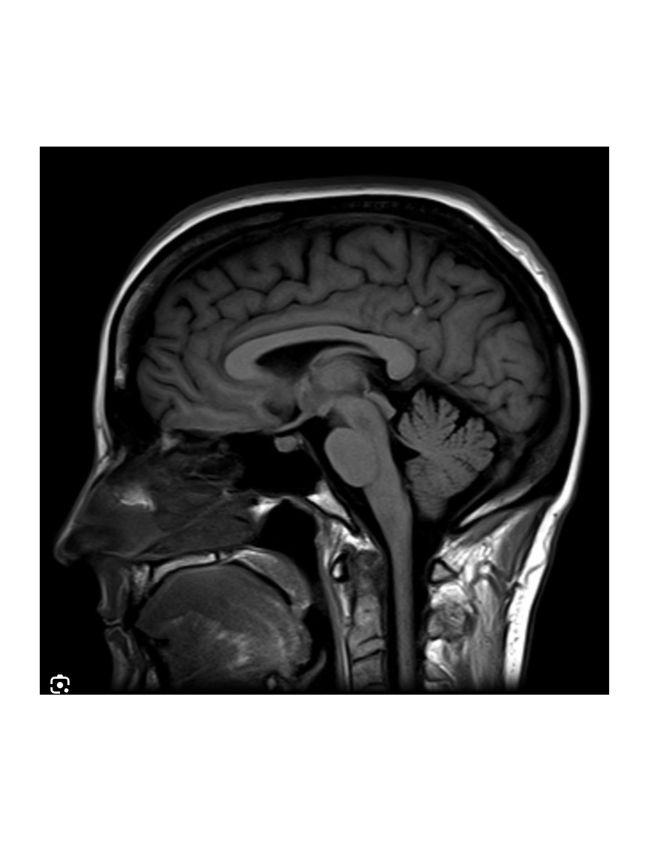

Yoga has been shown to treat low back pain as effectively as physical therapy, epidural injections, and even surgery, and low back pain is the most common medical reason for beginning yoga. Yet treating low back pain is not for beginners. Not at all. The symptoms of two conditions may be identical, yet their treatment be diametrically opposed: Herniated disc and spinal stenosis present my favorite example. The treatment that's good for one is precisely wrong for the other, although both may present with sciatica, numb feet, weakness in the legs, and back pain. But you don't usually need an MRI to tell the difference: An educated eye, an inquisitive interview and sound judgement will usually enable a careful clinician to determine what's causing the pain, and what to do about it.